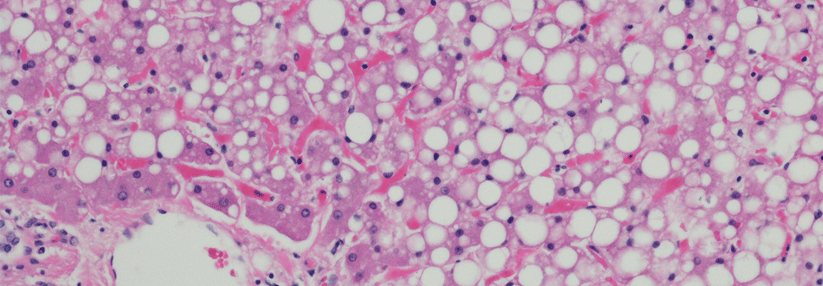

Die Fettleber ist Vorstufe der Steatohepatosis beim metabolischen Syndrom. Jeder vierte Deutsche ist betroffen, Tendenz steigend. Gewichtsverlust beseitigt das Problem effektiv - wenn die Patienten Disziplin zeigen.

Die nicht alkoholische Fettlebererkrankung (NAFLD) gilt als hepatische Manifestation des metabolischen Syndroms. Die NAFLD ist häufig mit einer Insulinresistenz assoziiert, die ihrerseits wiederum die Progression der Fettlebererkrankung fördert.

Entsprechend tragen Fettleber-Patienten ein erhöhtes Risiko für Typ-2-Diabetes und kardiovaskuläre Erkrankungen. Angesichts der ungebremsten Übergewichtsepidemie ist es kaum verwunderlich, das 20–30 % der Gesamtbevölkerung auch eine zu gut ernährte Leber aufweisen. Unter morbid Adipösen steigt diese Rate sogar über 90 %, schreibt das Team um Professor Dr. Christa Büchler vom Universitätsklinikum Regensburg.